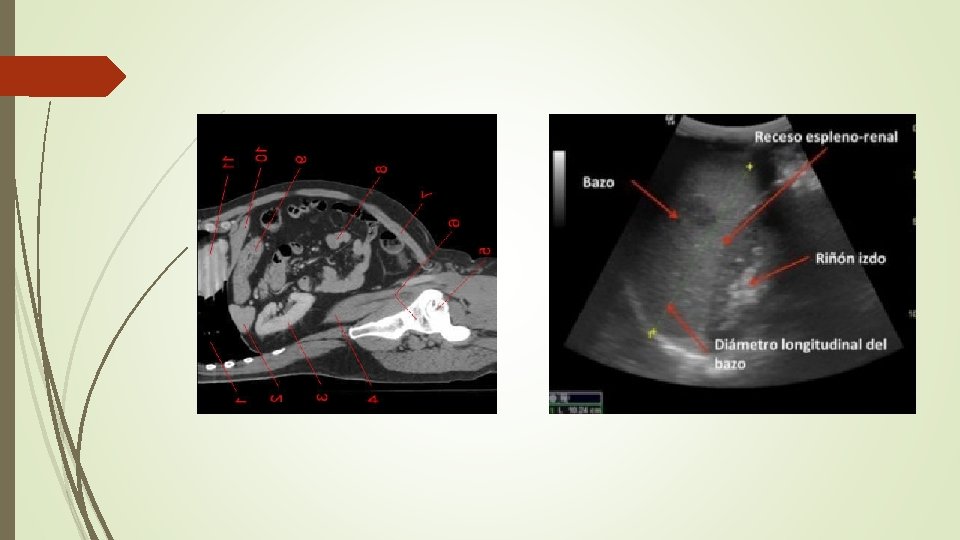

2. - RECESO ESPLENORRENAL Plano SAGITAL, línea axilar posterior izquierda 8ª-10ª costilla. CRANEAL CAUDAL

Evaluar 1. Liquido subdiafragmático/ supraesplenico (localización más frecuente)

2. Liquido en receso esplenorrenal 3. Liquido polo inferior riñón izquierdo